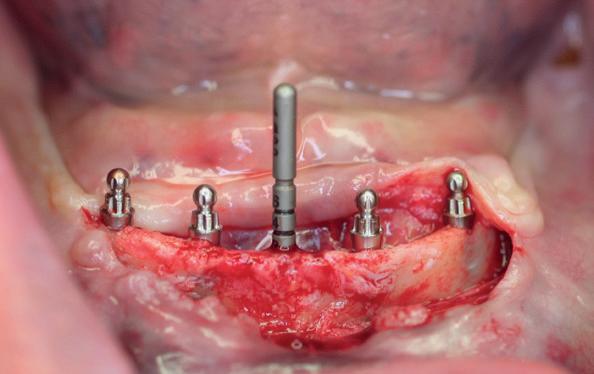

Chirurgie plaatsen van de 6 implantaten

Voor de behandeling kreeg de patiënt Amoxicilline 500mg 3dd1 gedurende een week voorgeschreven waarbij er een dag voor de chirurgie gestart werd, als pijnstilling Ibuprofen 600 mg 3dd1 voor een week en Blue M Mouthwash voor de mondspoeling gedurende de eerste 2 weken. Na de anesthesie werd een incisie gemaakt van tuber tot tuber en werd de

3. Na flap een guide pin in foramen incisivum

4. Plaatsen van 6 implantaten en kaakverbreding 14

5. Primaire sluiting met een door-

mucosa zowel buccaal als palatinaal afgeschoven. Het is belangrijk om te realiseren dat de bovenkaak zachter alveolair bot heeft dan de onderkaak en dat stug periost op de kaak kan zitten. Daarom is het van belang om te starten met curettage van de kaak. Na het vrijleggen van de canalis incisivum, werd een guide pin in de canalis geplaatst. Het kanaal loopt loodrecht op de kaak en kan dienen als referentie

lopende hechting

10. Setup van tijdelijke brug in het gezicht

voor de implantaten (afbeelding 3). Hierna werd met een meetinstrument de locaties van de implantaten uitgemeten en werd een initiële osteotomie op deze locaties gemaakt. Voor de 16 werd een crestale sinusbodemelevatie met Densah boren uitgevoerd. Hierbij werd het zachte bot gecondenseerd om naar crestaal geduwd te worden, waarna het membraan van Schneider meelifte. Door de osteotomie werden 1cc botkorrels geplaatst en daarna direct het implantaat. Ter plaatse van de 14 zat een verticaal botdefect, na plaatsen van dit implantaat, werd de kaak verticaal verhoogd. Er werden 6 implantaten van het merk AnyRidge (MegaGen Implant Company, Korea) geplaatst met diameter 5.0 mm aan de distale zijdes, diameter 4.5 mm bij de premolaren en 4.0 mm implantaten bij de laterale incisieven (afbeelding 4).

Ter plaatste van de 16 en 14 werden verticale matrashechtingen geplaatst, waarna er één doorlopende hechtingen van tuber tot tuber volgde met een 4-0 gevlochten hechtdraad (afbeelding 5). Gedurende de eerste 2 weken van de genezing is het van essentieel belang voor de wondgenezing, dat de patient geen bovenprothese draagt. Deze werd daarom ingenomen, met de uitleg dat direct dragen van de bovenprothese een nadelige invloed heeft op de genezing van de kaak, de botopbouw en de implantaten. Patiënt kwam 2 weken na de chirurgie retour voor het verwijderen van de hechtingen, waarna de binnenzijde van de bovenprothese werd uitgeslepen en voorzien werd van een softliner als nieuwe tijdelijke voering voor retentie van de bovenprothese. Vanwege de kaakverhoging en sinusbodemelevatie, werd 6 maanden genezing afgewacht van het bot en integratie van de implantaten.